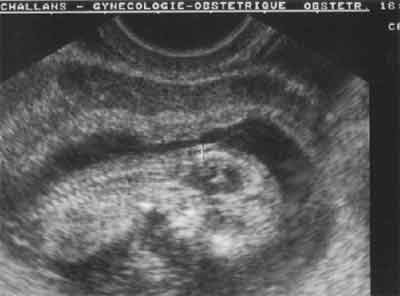

Coupe longitudinale 75 % de l'image